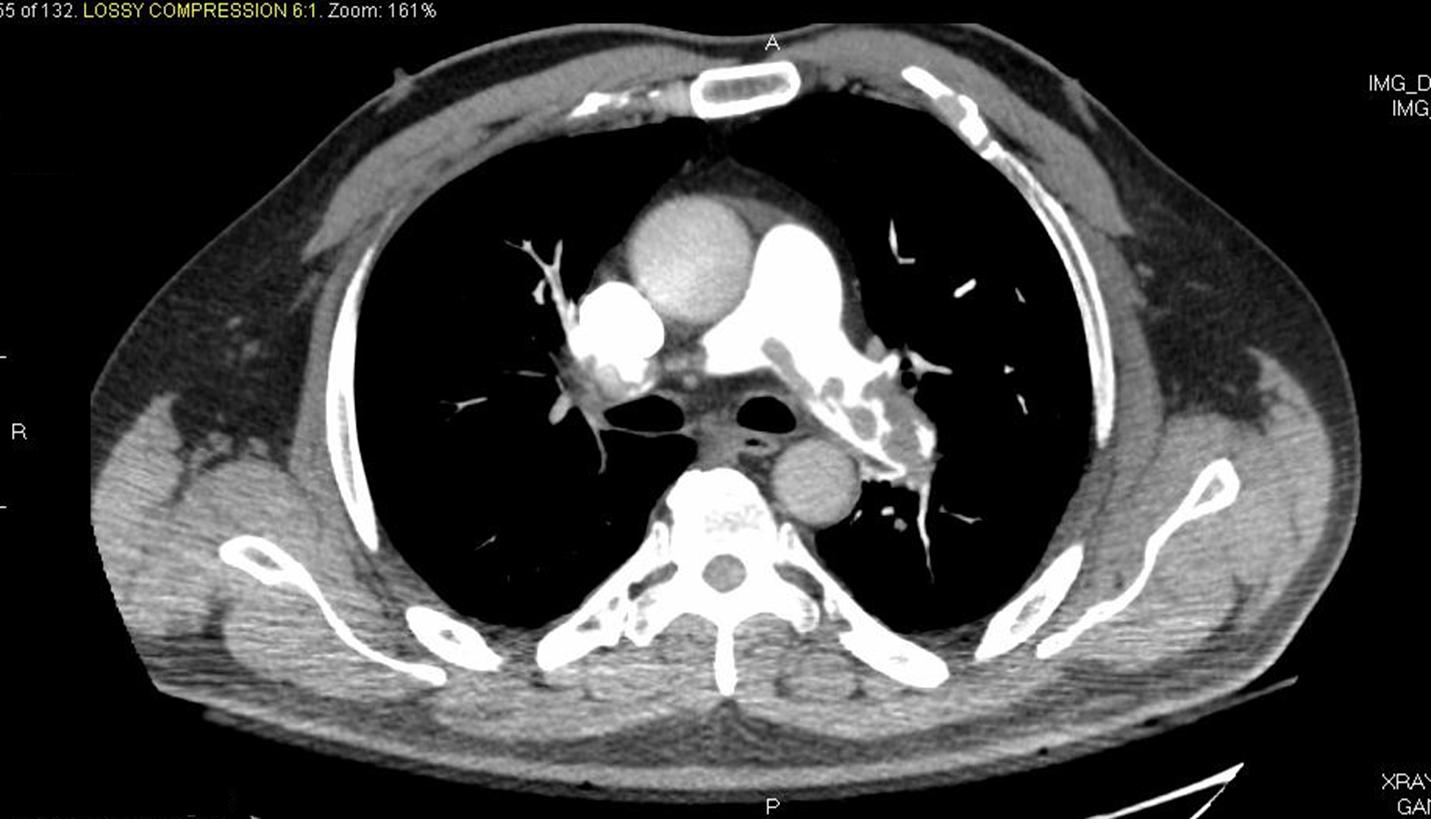

Imaging studies that are used for making the diagnosis of VTE include duplex ultrasound (of the legs), CT angiography / venography, MR angiography and ventilation-perfusion scanning. Although all of these tests are quite accurate, one must move to more imaging studies if there is a high level of suspicion for VTE and one test was negative.

Pulmonary emboli (PE)

Pulmonary embolism refers to blood clots that lodge in the arteries of the lungs. Pulmonary emboli most commonly originate from the deep veins of the legs. Therefore the main cause for pulmonary embolism is a deep vein thrombosis. The deep vein thrombosis that causes pulmonary embolism may go unnoticed or be symptomatic. Therefore, it is not always diagnosed. On the other hand this is the reason for both pulmonary emboli and deep vein thrombosis to be considered part of the same disease spectrum (i.e. venous thromboembolism).